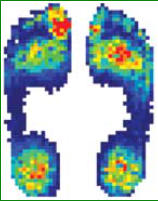

Bei der Schuhinnendruckmessung lassen sich die

real wirkenden Kräfte zwischen Fuß und Schuh in der

Statik und Dynamik mit einer leicht verständlichen

Darstellung erklären. Diese Daten sind besonders bei

einer Neurophatie sehr hilfreich um Druckstellen zu

erkennen und zu beheben.

Innendruckmessung

Mit dieser Methode werden ihre

Füße, unter Verwendung einer

Messsohle im Schuh, in Statik

und Dynamik vermessen um

Druckspitzen festzustellen.